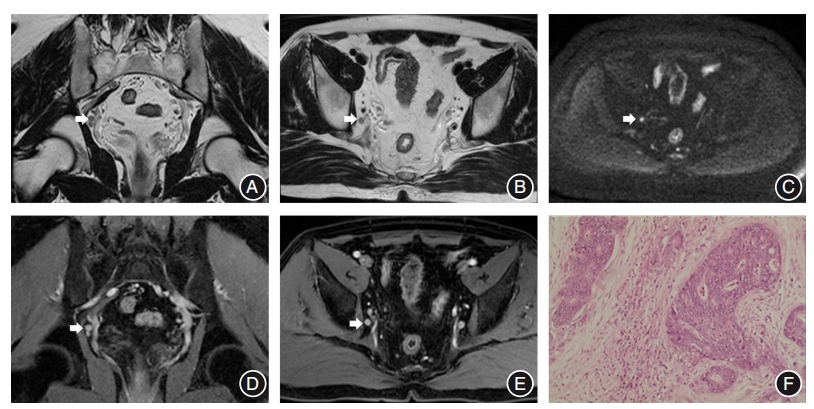

目的 探究联合术前磁共振成像(MRI)和术后病理评估淋巴结转移预测直肠癌总生存期的价值。 方法 回顾性收集2016年1月至2021年12月2610例在中山大学附属第六医院组织病理学证实为直肠腺癌患者的临床、病理和影像学资料。所有患者均行MRI检查,并根据淋巴结术前MRI( MRI N)和术后病理( P N)评估的转移情况将患者分为3组:MRI N+但 P N-( MRI N+组)、 P N+但 MRI N-( P N+组)和 MRI N+且 P N+( MRI-P N+组)。使用逆概率加权(IPW)校正混杂因素。采用Kaplan-Meier曲线估计总生存率,并用log-rank检验进行组间比较。使用单因素Cox回归模型分析肿瘤特征与总生存期的相关性,采用双向逐步Cox回归模型确定总生存期的独立危险因素。 结果 MRI-P N+组比 P N+组、 MRI N+组具有更高的肿瘤分期、更频繁的神经周围侵犯、更多的远处转移和更高的死亡风险(均P < 0.05)。Kaplan-Meier曲线显示 MRI N+组、 P N+组和 MRI-P N+组的3年生存率分别为90.5%、79.1%和76.4%;5年生存率分别为85.7%、71.5%和59.2%。双向逐步Cox回归分析显示年龄、肿瘤位置、癌胚抗原、糖类抗原19-9、淋巴结送检个数、病理肿瘤分期、脉管内癌栓、神经周围侵犯、远处转移、新辅助治疗和辅助治疗、MRI-病理淋巴结转移是影响直肠癌患者总生存期的独立危险因素(均P < 0.05)。 结论 联合术前MRI和术后病理评估淋巴结转移有助于更准确预测直肠癌患者的总生存期。

Objective To investigate the value of combining preoperative magnetic resonance imaging(MRI) and postoperative pathological assessment of lymph node metastasis in predicting overall survival in rectal cancer patients. Methods This retrospective study collected clinical, pathological and image information of 2610 patients histopathologically confirmed with rectal adenocarcinoma at the Sixth Affiliated Hospital of Sun Yat-sen University between January 2016 and December 2021. All patients underwent MRI scans and were divided into three groups according to lymph node status assessed by preoperative MRI( MRI N) and postoperative pathology( P N): MRI N+ but P N-( MRI N+ group), P N+ but MRI N-( P N+ group), MRI N+ and P N+( MRI-P N+ group). Inverse probability weighting(IPW) was used to adjust for confounding factors. Kaplan-Meier curves were used to estimate overall survival and log-rank tests were used to compare the difference. Univariate Cox regression models were used to analyze the correlation between tumor characteristics and overall survival, and bidirectional stepwise Cox regression models were used to identify independent risk factors for overall survival. Results The MRI-P N+ group showed higher tumor staging, more frequent perineural invasion, more distant metastases, and a higher risk of death compared to the P N+ group and MRI N+ group(all P < 0.05). Kaplan-Meier curves showed that the 3-year survival rates for the MRI N+ group, P N+ group, and MRI-P N+ group were 90.5%, 79.1%, and 76.4%, respectively; the 5-year survival rates were 85.7%, 71.5%, and 59.2%, respectively. Stepwise Cox regression showed that age, tumor location, carcinoembryonic antigen, carbohydrate antigen 19-9, lymph nodes number, pathological tumor stage, lymphovascular invasion, perineural invasion, distant metastasis, neoadjuvant therapy and adjuvant therapy, and MRI-pathology lymph node status were independent risk factors for overall survival in rectal cancer(all P < 0.05). Conclusion Evaluating the lymph node status by combining preoperative MRI and postoperative pathology helps predict overall survival in rectal cancer patients more accurately.